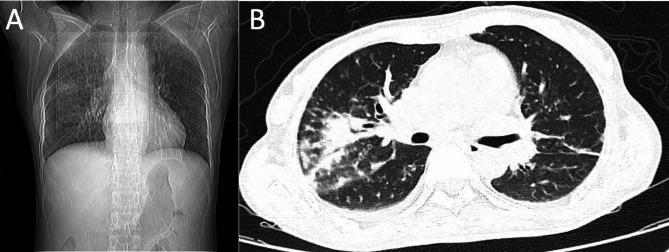

A 52-year-old woman presented with a fever, which has persisted for the past eight days, along with worsening shortness of breath and decreased blood pressure. Computed tomography (CT) revealed an air bronchogram, lung consolidation, and bilateral pleural effusion. The subsequent polymerase chain reaction (PCR) of the bronchoalveolar lavage fluid (BALF) revealed positivity for H5N1 and severe acute respiratory syndrome coronavirus 2 (SARS-CoV-2).

The H5N1 influenza virus is a cause of severe pneumonia. The clinical presentation of the patient had a predomination of H5N1 influenza rather than COVID-19. A PCR analysis for the identification of the virus is necessary to reveal the pathogen causing the severe pneumonia. The patient exhibited an excellent prognosis upon the use of the appropriate antiviral medicine.

一名 52 岁女性因发热持续 8 天,伴呼吸困难加重和血压下降而就诊。计算机断层扫描(CT)显示空气支气管征、肺部实变和双侧胸腔积液。随后对支气管肺泡灌洗液(BALF)的聚合酶链反应(PCR)显示 H5N1 和严重急性呼吸综合征冠状病毒 2(SARS-CoV-2)均呈阳性。

H5N1 流感病毒可引起严重肺炎。患者的临床表现以 H5N1 流感为主,而不是 COVID-19。进行病毒 PCR 分析对于确定引起严重肺炎的病原体是必要的。该患者使用适当的抗病毒药物后预后良好。